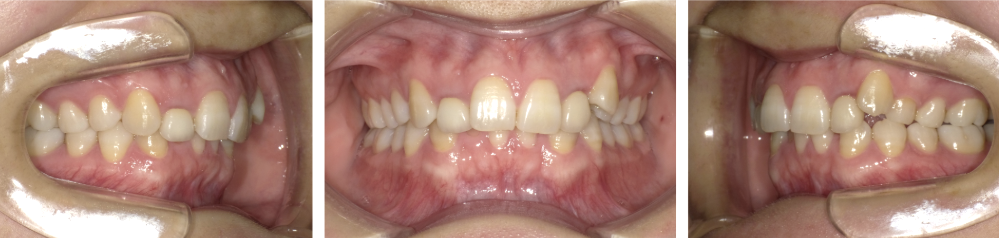

過蓋咬合中等度症例画像

中等度(下の前歯が半分以上隠れる)の方の場合

下の前歯が上の前歯に大きく隠れており、笑ったときに下の前歯がほとんど見えない。また、前歯で噛み切りにくく、奥歯に負担がかかりやすい状態では、前歯の高さや角度の調整、奥歯の高さコントロール、必要に応じて歯列の幅や前後的な位置の調整を行い、縦方向と前後方向の調整が増えるため、ワイヤー矯正を中心に治療を進めることが多いです。 場合によってはマウスピース型矯正装置と併用することもあります。 治療期間は約1年〜1年半程度が目安です。

過蓋咬合重度症例画像

重度(下の前歯がほとんど見えない・歯茎に当たる)の方の場合

噛んだときに下の前歯がほとんど見えず、上の前歯の裏側が下の歯茎に当たって痛むことがあり、顎関節の違和感や歯のすり減りが気になる「深く噛み込みすぎている」状態では、奥歯の沈めるコントロールや前歯の角度と高さの調整、必要に応じてアンカースクリューや顎矯正手術の併用が必要となります。 治療期間は1年半〜2年半程度と長めになりますが、その分、かみ合わせや口元のバランスを丁寧に整えることができます。 ご自身では判断しにくいため、当院では写真やレントゲン・模型を使い、現在の状態と治療の選択肢をわかりやすくご説明しますので、気になる方は早めにご相談ください。